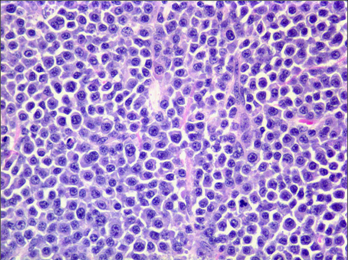

Question 33

Question

Which type of round cell tumour is this? Note presence of eosinophils

Answer

• Mast cell tumour

• Plasmacytoma

• Histiocytoma

• Lymphoma